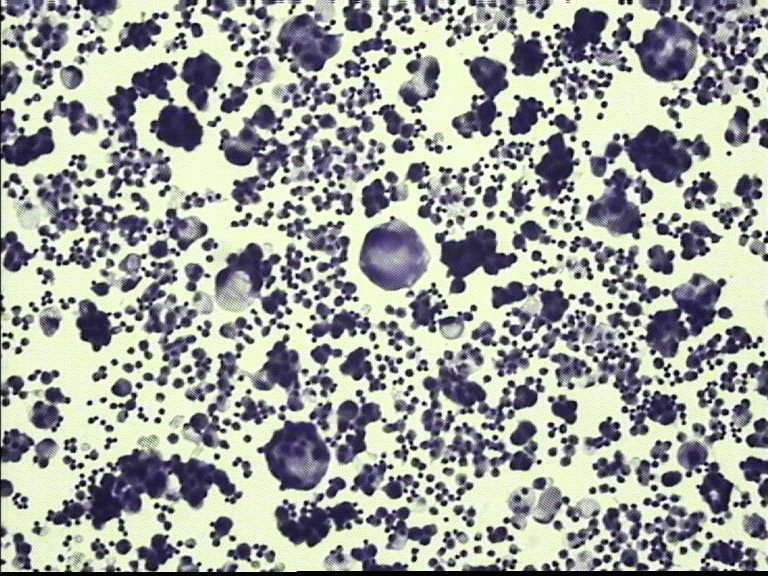

胸水 男67岁

• 胸水 男67岁图4

图4